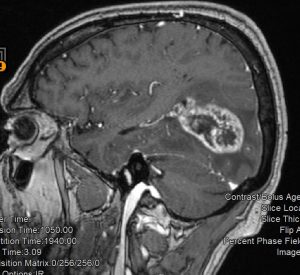

Ασθενής άνδρας, 65 ετών ο οποίος παρουσίασε αρχικά αίσθημα κόπωσης και διαλείπουσες κεφαλαλγίες. Ο νευροαπεικονιστικός έλεγχος με μαγνητική τομογραφία με σκιαγραφικό ανέδειξε χωροκατακτητική εξεργασία στην περιοχή του αριστερού σφηνοειδούς λοβίου με επέκταση και υποεπενδυματική διήθηση του ινιακού κέρατος.

Η μετεγχειρητική μαγνητική τομογραφία εγκεφάλου )βλ. εικόνα) εντός 48ωρου επιβεβαιώνει την ολική εξαίρεση του όγκου.